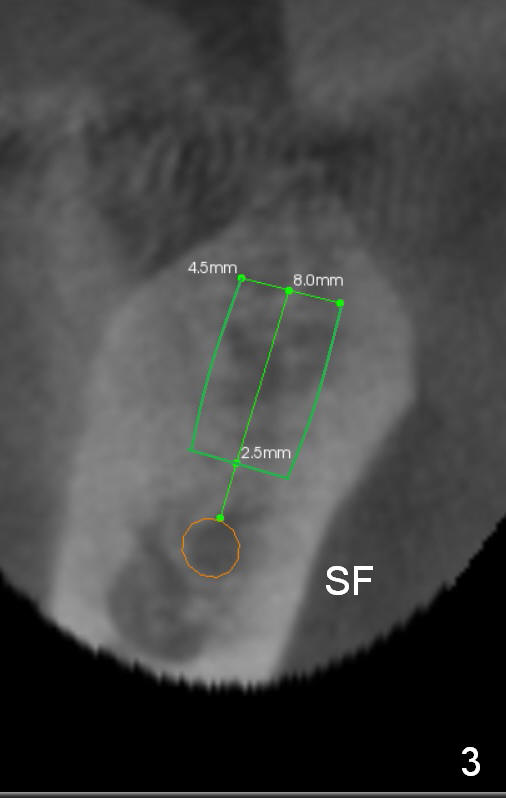

Before crown removal, use the 3.5 mm (vs. normally 5 mm) implant spacer and #15 to mark an entrance point for #31 implant (make a cross over the crestal gingiva). After crown removal, insert a 3 mm Guide Pin into #30 implant well as a parallel pin. Use 2 mm pilot drill to start osteotomy through the cross and then make incision. While drilling and reaming, pay attention to the submandibular fossa (Fig.3 SF) and the Inferior Alveolar Canal (orange). When a 4.5x8 mm implant is placed, place abutments and make splinted provisional.